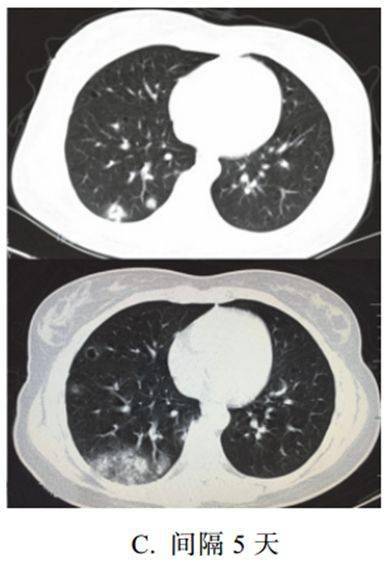

新冠肺炎大多数病例进展迅速,复查 CT 影像发生明显变化

表现为病灶数目明显增多,范围明显扩大,密度增高,病灶分布由外周向中央推进

根据既往 SARS 病理学机制,提示为肺泡腔内聚集大量细胞渗出液、间质内血管扩张渗出;肺泡连通起来形成融合态势(图 2-11)

图 2-11 病灶数目增多、范围扩大 (A-D)